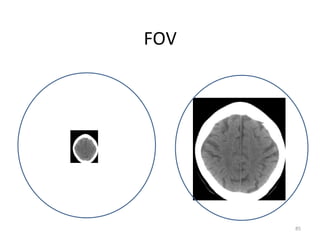

FOV

• Para cada região estudada, deve-se usar um

FOV.

• Ex:

Crânio = 22cm

Tórax = 35cm

Abdome = 40cm

Joelho = 18cm

Seios da face = 14cm

85